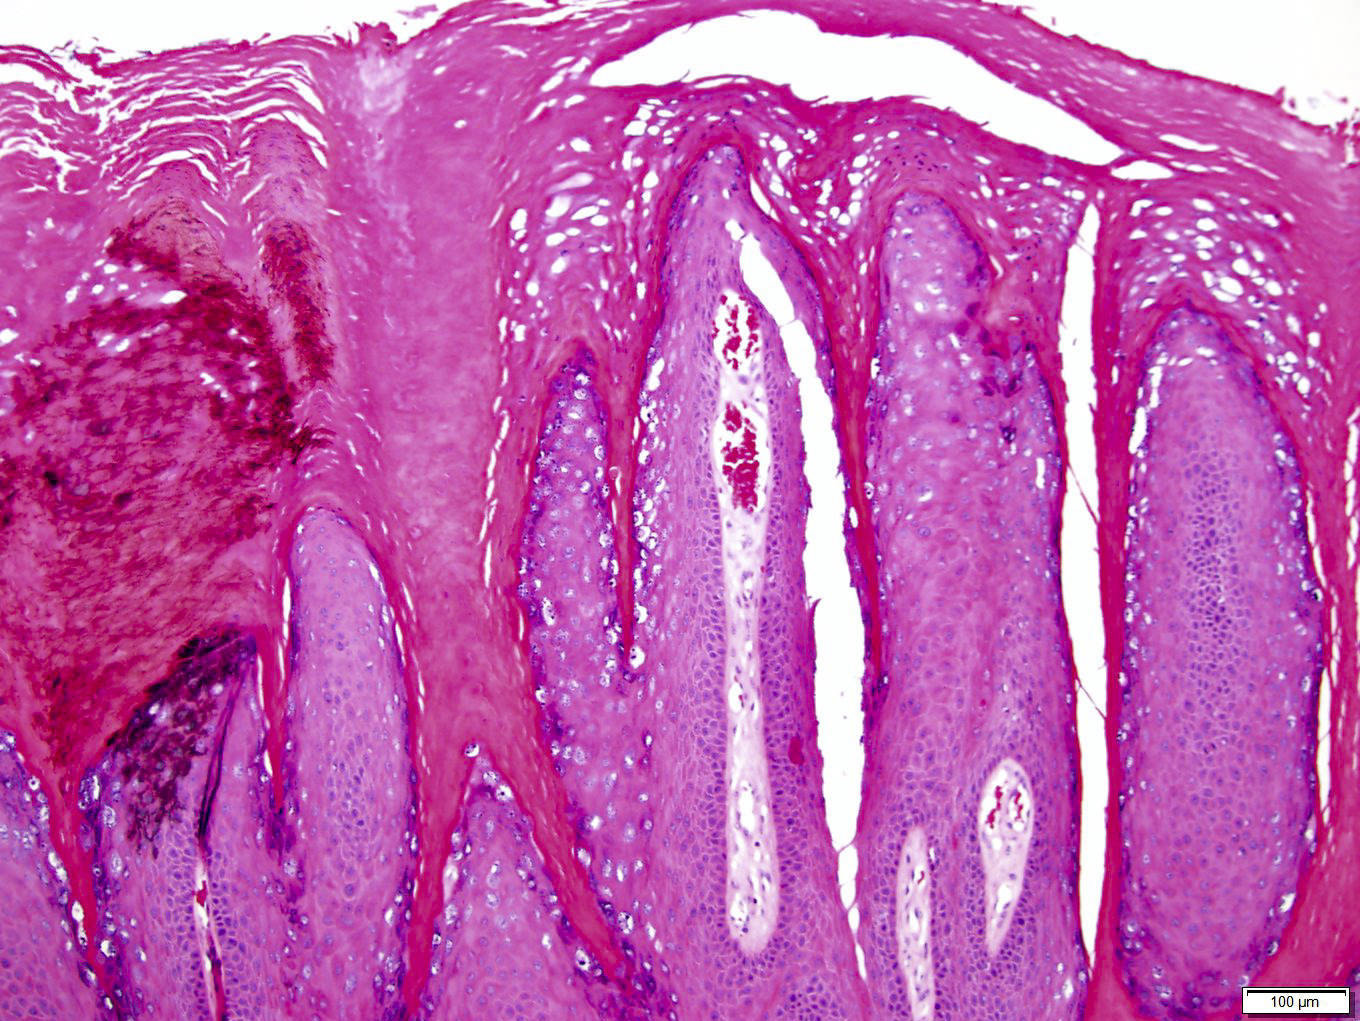

Microscopic (histologic) description

- Common warts (verruca vulgaris) (Arch Pathol Lab Med 2018;142:700):

- Hyperkeratosis, papillomatosis, hypergranulosis

- Columns of parakeratosis, especially over projecting dermal papillae

- Intracorneal hemorrhage

- Vacuolated superficial keratinocytes with pyknotic raisin-like nuclei (koilocytes)

- Koilocytes may not be seen in older lesions

- Koilocytes are not needed for the diagnosis

- Inward bending of rete ridges at borders of lesion (toeing in)

- Dilated capillaries in dermal papillae

- Projects above the plane of the epidermis

Microscopic (histologic) images

Contributed by Heba Ahmed Abdelkader, M.D., Hillary Rose Elwood, M.D., AFIP,

@MirunaPopescu13 on Twitter and @shilpa_rakesh_path on Instagram